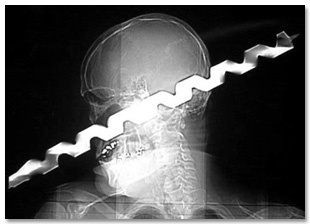

3. 被46公分的钻头穿过脑袋

2003年,建筑工杭特(Ron Hunt)在一起意外中被46公分的钻头穿过脑门。他因此失去了一只眼睛,但神奇的是,他没死。